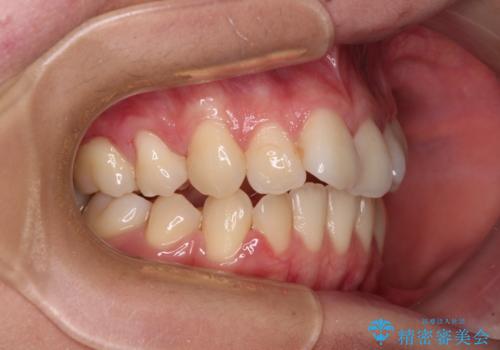

- 抜歯矯正の後戻りを気にして来院された患者様です。

舌の突出癖によるオープンバイトになっていたため、インビザラインによるマウスピース矯正をおすすめしましたが、自己管理の自信がないとのことで、ワイヤー装置による矯正治療を行うこととしました。

舌の突出癖が認められると、上下前歯の隙間を閉じることができません。

舌のトレーニングをしっかりと行っていただくことで、歯列を整えることができます。